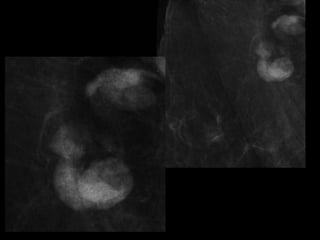

LUS โ€“ Cephalic

POSTNATAL BABYGRAM

-Cephalic

-Heart - right side

-Stomach โ€“ right side

-Liver โ€“ left side

-Des colon โ€“ right side

Situs Inversus Totalis

-Cephalic -Heart - rightside -Stomach โ€“ right side -Liver โ€“ left side -Des colon โ€“ right side

Situs Inversus Totalis โ€ข3-5% with cardiac abnormalities โ€ข 25% with primary ciliary dyskinesia (PCD) โ€“ Kartagenerโ€Ÿs Syndrome โ€“ Chronic sinus infections; respiratory infections; infertility